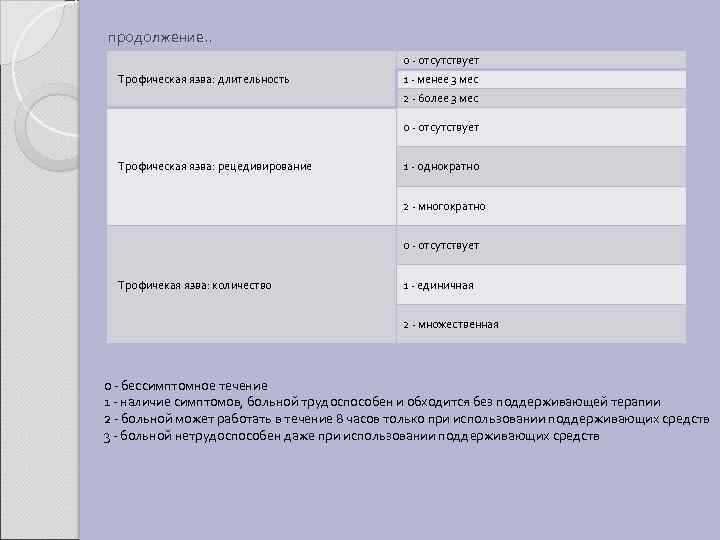

продолжение. . 0 - отсутствует Трофическая язва: длительность 1 - менее 3 мес 2 - более 3 мес 0 - отсутствует Трофическая язва: рецедивирование 1 - однократно 2 - многократно 0 - отсутствует Трофичекая язва: количество 1 - единичная 2 - множественная 0 - бессимптомное течение 1 - наличие симптомов, больной трудоспособен и обходится без поддерживающей терапии 2 - больной может работать в течение 8 часов только при использовании поддерживающих средств 3 - больной нетрудоспособен даже при использовании поддерживающих средств